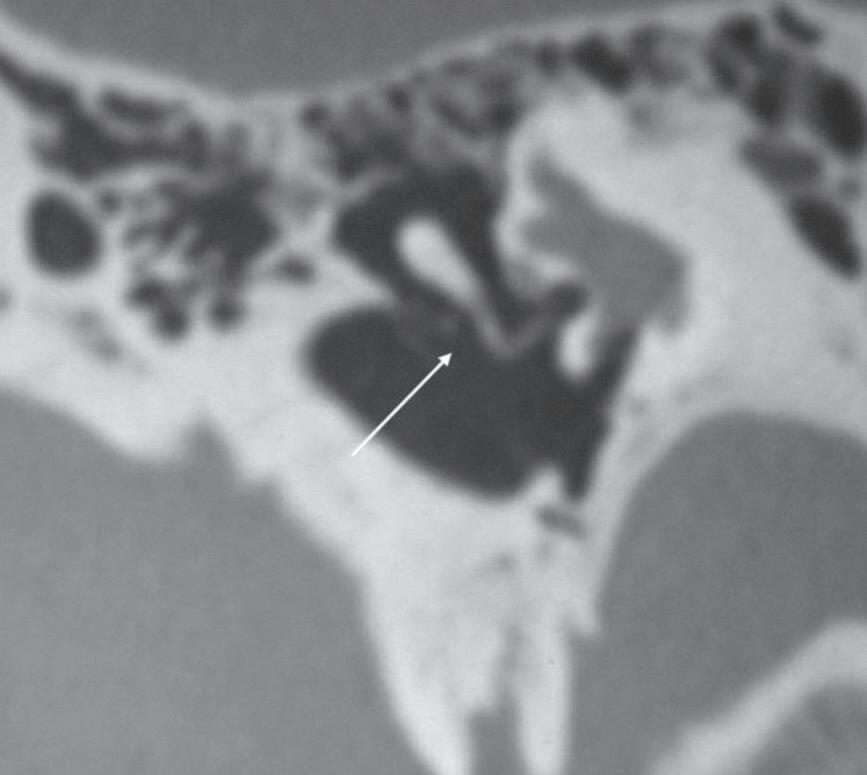

Fig. 1-2. Cadeia ossicular sem e com reformação oblíqua. (a) Tomografia computadorizada de osso temporal, corte coronal, janelamento ósseo, cabeça do martelo sem reformações (seta). (b) Tomografia computadorizada de osso temporal, corte coronal, janelamento ósseo, corpo da bigorna sem reformações (seta). (c) Tomografia computadorizada de osso temporal, corte axial, janelamento ósseo, estribo sem reformação (seta). (d-f) Tomografia computadorizada com reformações coronal e axial oblíquas no eixo da cadeia ossicular, martelo, bigorna e estribo com melhor definição.